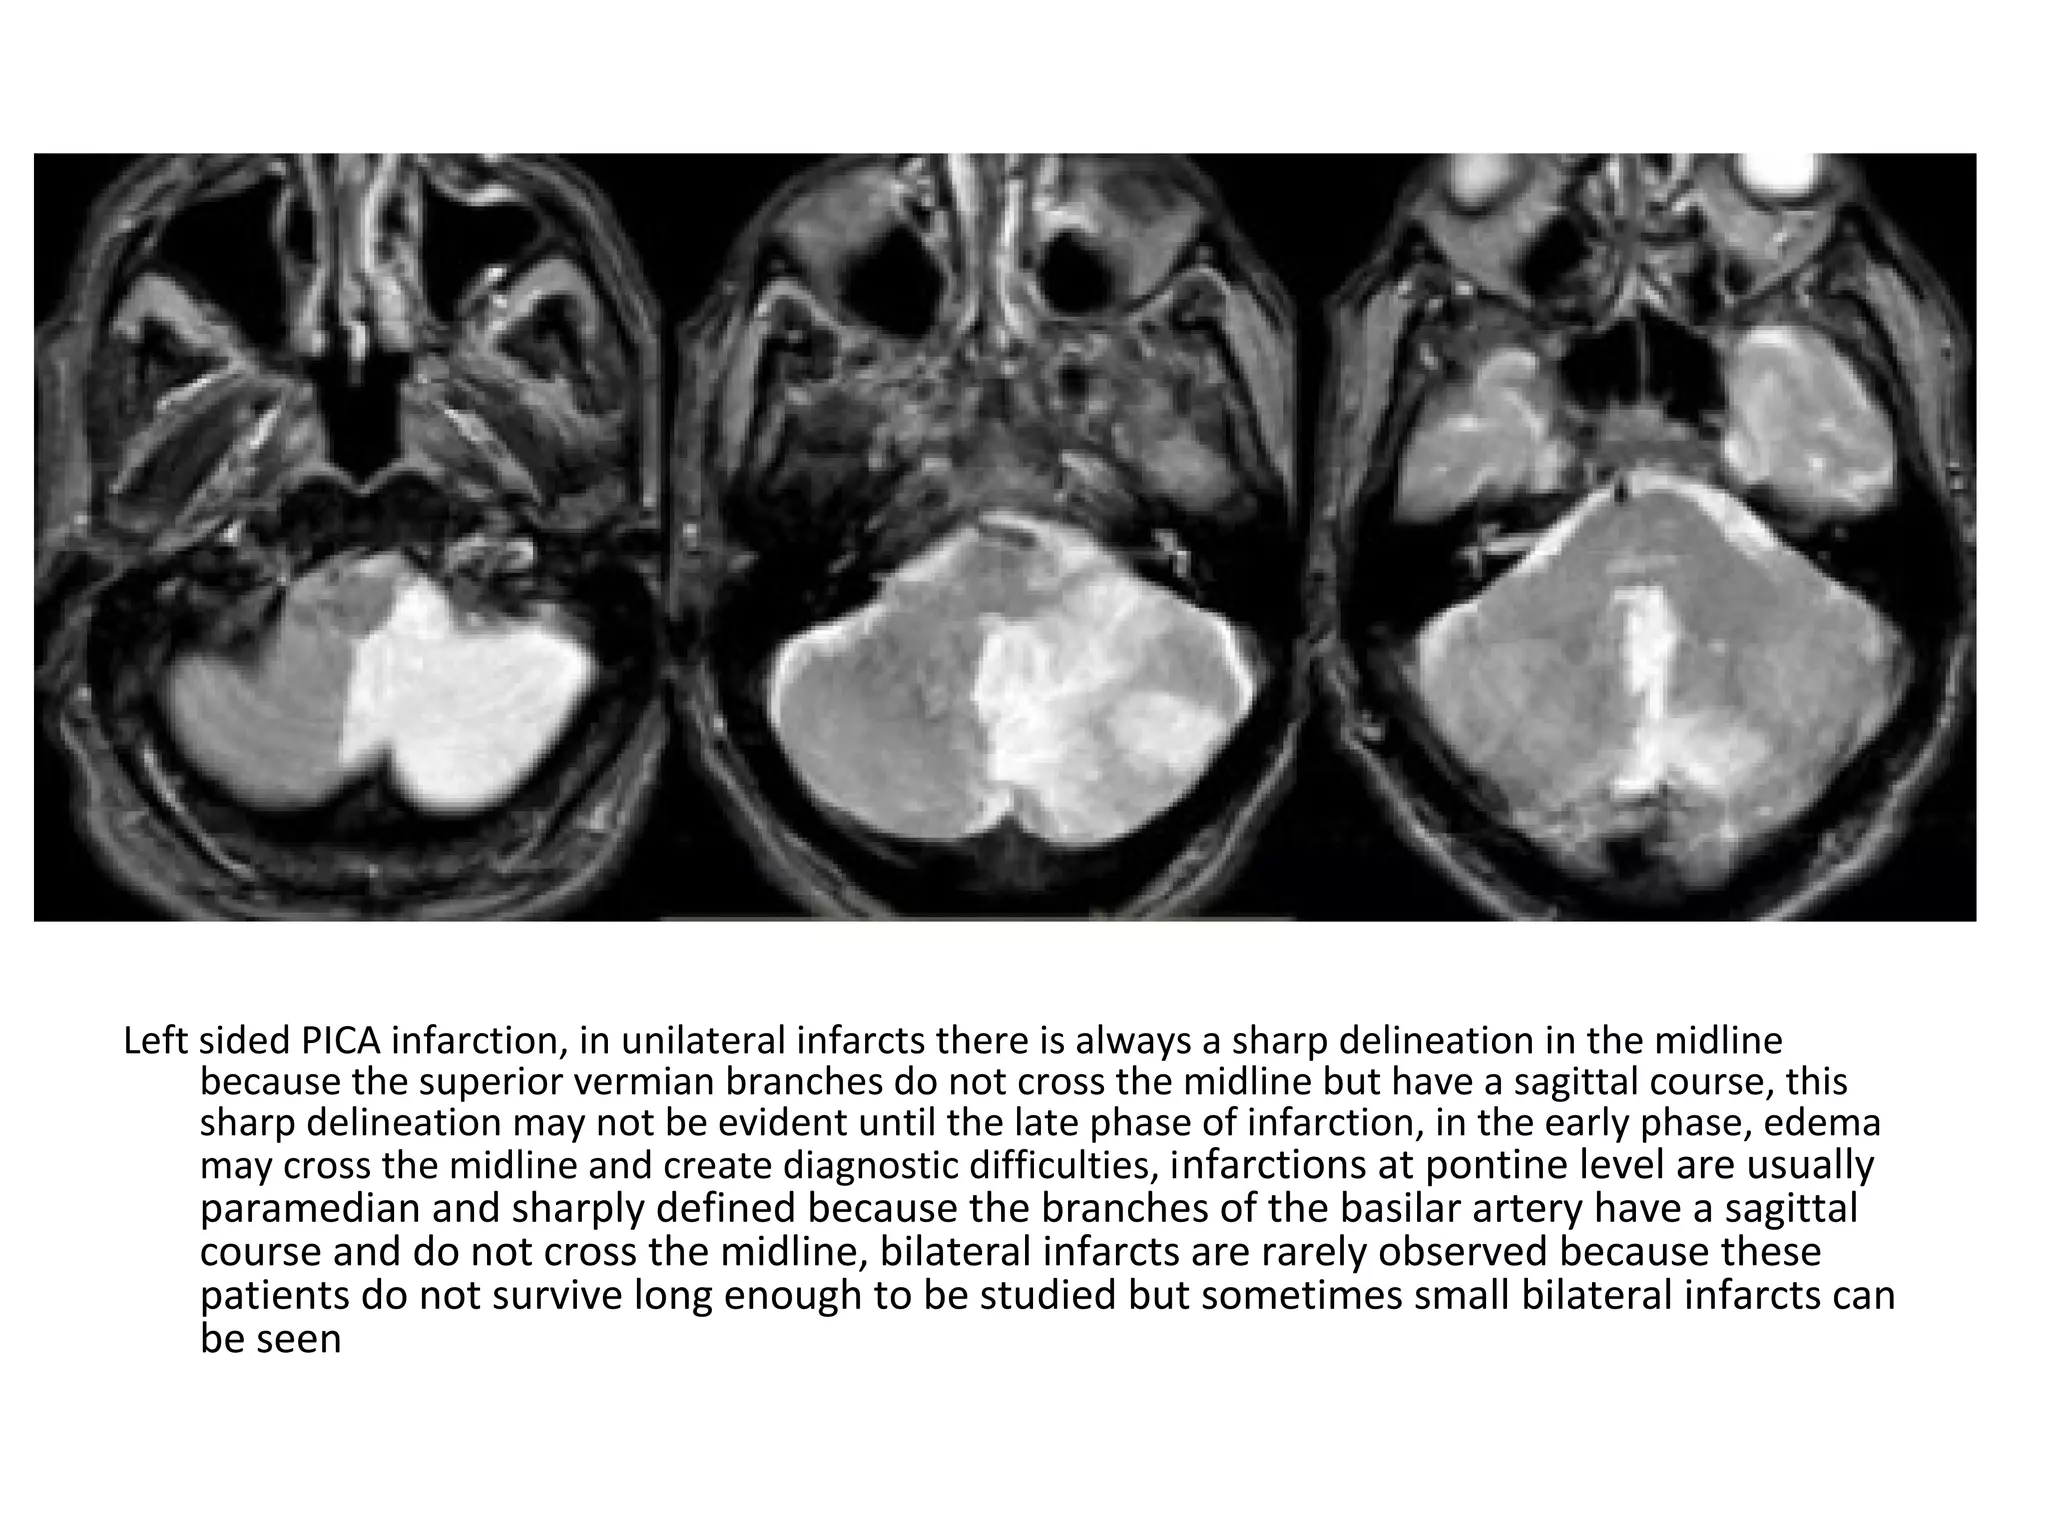

1-Posterior Inferior Cerebellar Artery (PICA in blue)

-The PICA territory is on the inferior occipital

surface of the cerebellum and is in equilibrium

with the territory of the AICA in purple which

is on the lateral side

-The larger the PICA territory , the smaller the

AICA and vice versa

Left-sided PICA infarction , notice the posterior extension , the

infarction was the result of a dissection (blue arrow)

Left sided PICA infarction, in unilateral infarcts there is always a sharp delineation in the midline

because the superior vermian branches do not cross the midline but have a sagittal course, this

sharp delineation may not be evident until the late phase of infarction, in the early phase, edema

may cross the midline and create diagnostic difficulties, infarctions at pontine level are usually

paramedian and sharply defined because the branches of the basilar artery have a sagittal

course and do not cross the midline, bilateral infarcts are rarely observed because these

patients do not survive long enough to be studied but sometimes small bilateral infarcts can

be seen